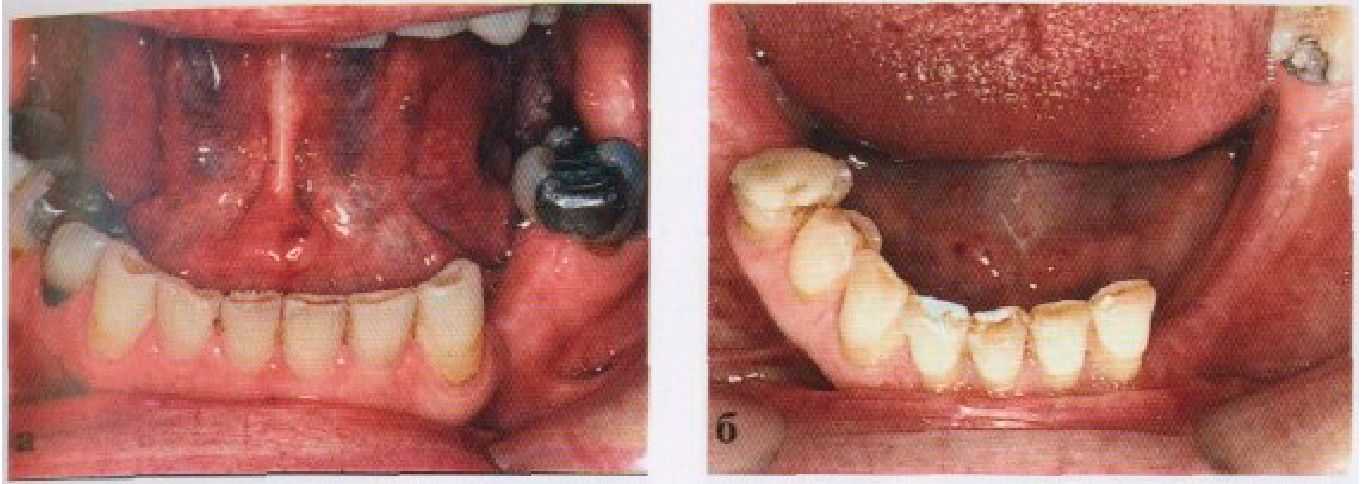

Рис. 3-4. Варианты опоры для частичных съемных протезов, (а) Опора на зубы с помощью окклюзионных накладок, вызывающая вертикальный вектор нагрузки на челюстную кость через периодонт. (б) Компрессия кости, возникающая в результате опоры базиса частичного съемного протеза на слизистую оболочку, (в) Сочетание опоры на зуб и слизистую оболочку, имеющее место у частичных съемных протезов с концевыми седлами.

Рис. 3-5. Выбор опорных зубов, (а) Клыки и моляры являются отличными потенциальными опорными зубами для включенного дефекта зубного ряда, (б) Наклоненные моляр и боковой резей не могут быть использованы в качестве адекватных опорных зубов для данного включенного дефекта большой протяженности. Их нужно сочетать с опорой на слизистую оболочку. Сочетание опоры на зуб и на слизистую оболочку — лучший вариант, который может быть создан для концевого дефекта зубного ряда справа.

опорный зуб может выдержать свою собственную жевательную нагрузку в совокупности с нагрузкой полутора искусственных зубов. Клыки, первые и вторые моляры обеспечивают надежную опору, тогда как все нижние резцы и боковые верхние резцы представляют собой слабую опору, хотя, в свете ранее имевшегося заболевания пародонта, ситуация может изменяться (рис. 3-5).